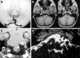

Tortuous vertebral artery

The posterior spinal artery (dorsal spinal arteries) arises from the vertebral artery in 25% of humans or the posterior inferior cerebellar artery in 75% of humans, adjacent to the medulla oblongata. It supplies the grey and white posterior columns of the spinal cord. [Source: Wikipedia ]